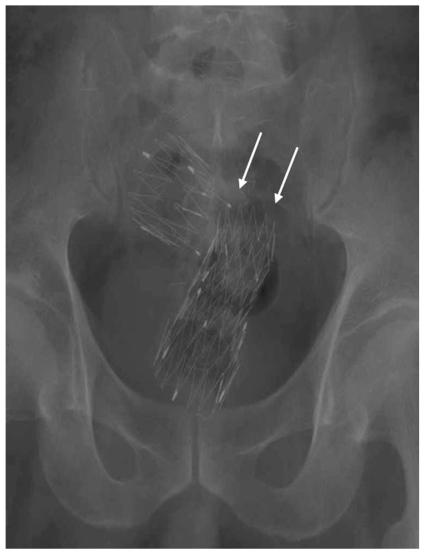

We wanted to evaluate usefulness of uncovered stent in comparison with covered stent for the palliative treatment of malignant colorectal obstruction.

Covered (n = 52, type 1 and type 2) and uncovered (n = 22, type 3) stents were placed in 74 patients with malignant colorectal obstruction. Stent insertion was performed for palliative treatment in 37 patients (covered stent: n = 23 and uncovered stent: n = 14). In the palliative group, the data on the success of the procedure, the stent patency and the complications between the two groups (covered versus uncovered stents) were compared.

RESULTS

The technical success rate was 89% (33/37). Symptomatic improvement was achieved in 86% (18/21) of the covered stent group and in 92% (11/12) of the uncovered stent group patients. The period of follow-up ranged from three to 319 days (mean period: 116+/-85 days). The mean period of stent patency was 157+/-33 days in the covered stent group and 165+/-25 days in the uncovered stent group. In the covered stent group, stent migration (n = 11), stent fracture (n = 2) and poor expansion of the stent (n = 2) were noted. In the uncovered stent group, tumor ingrowth into the stents (n = 3) was noted.

CONCLUSION

Self-expanding metallic stents are effective for relieving malignant colorectal obstruction. The rate of complications is lower in the uncovered stent group than in the covered stent group.